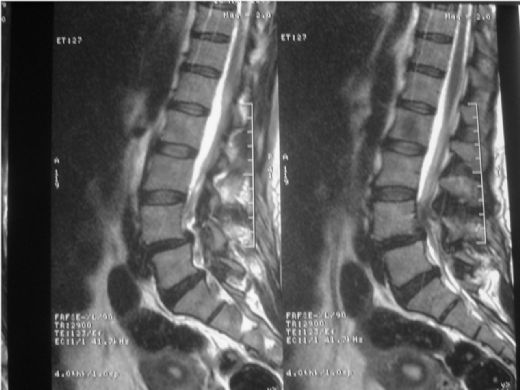

Bel fıtığı, omurgadaki disklerin kayması sonucu oluşan bir durumdur ve ciddi rahatsızlıklara yol açabilir. Manyetik Rezonans Görüntüleme (MR), bu durumu tanımlamak için etkili bir yöntemdir. MR, disk değişikliklerini, sinir kökü kompresyonunu ve inflamasyonu net bir şekilde gösterir, böylece uygun tedavi seçenekleri belirlenebilir.

Bel Fıtığı MR ÖzellikleriBel fıtığı, tıbbi literatürde "lumbar disk hernisi" olarak adlandırılan bir durumdur ve omurganın alt kısmında bulunan intervertebral disklerin, çevresindeki dokulara doğru kayması sonucu meydana gelir. Bu durum, genellikle bel ağrısı ve bacaklarda sinir kökü irritasyonuna bağlı olarak çeşitli semptomlarla kendini gösterir. Manyetik Rezonans Görüntüleme (MR), bel fıtığının tanı ve değerlendirilmesinde yaygın olarak kullanılan bir görüntüleme yöntemidir. Bel Fıtığı Nedir? Bel fıtığı, bel bölgesindeki disklerin, normal anatomik yerlerinden kayarak sinir köklerine baskı yapması sonucunda oluşan bir durumdur. Bu durum, genellikle şu şekillerde ortaya çıkabilir:

Bu durumlar, belde ağrı, bacaklarda uyuşma, karıncalanma ve güçsüzlük gibi çeşitli semptomlara yol açabilir. MR Görüntüleme Yöntemi Manyetik Rezonans Görüntüleme (MR), vücut içindeki dokuların ayrıntılı görüntülerini elde etmek için manyetik alanlar ve radyo dalgaları kullanan non-invaziv bir görüntüleme tekniğidir. MR, yumuşak dokuların görüntülenmesinde X-ışınlarına göre daha üstün sonuçlar verir. Bel fıtığı gibi durumların tanısında oldukça etkili bir yöntemdir. Bel Fıtığı MR Özellikleri Bel fıtığı MR görüntülerinde dikkate alınması gereken bazı önemli özellikler şunlardır:

MR Raporu ve Değerlendirme MR raporları, bel fıtığının ciddiyetini ve tedavi seçeneklerini belirlemek için kritik öneme sahiptir. Rapor, fıtığın boyutunu, konumunu ve çevresindeki yapılar üzerindeki etkisini içermelidir. Bu değerlendirme, cerrahi veya konservatif tedavi yöntemlerinin planlanmasında yardımcı olur. Sonuç Bel fıtığı, birçok bireyi etkileyen yaygın bir sağlık sorunudur ve MR görüntüleme, bu durumun tanı ve değerlendirilmesinde oldukça önemli bir rol oynamaktadır. Bel fıtığı MR özellikleri, tanı sürecinde doktorlara yardımcı olurken, doğru tedavi yöntemlerinin belirlenmesinde de kritik bir öneme sahiptir. Bu nedenle, bel fıtığı şikayetleri olan bireylerin, uzman bir hekim tarafından değerlendirilmesi ve gerekirse MR çekimi yapılması önerilmektedir. Ek olarak, bel fıtığı tedavisinde fizik tedavi, ilaç tedavisi ve gerektiğinde cerrahi müdahale gibi çeşitli seçenekler bulunmaktadır. Tedavi sürecinin bireye özel olarak planlanması, iyileşme sürecini hızlandıracak ve yaşam kalitesini artıracaktır. |